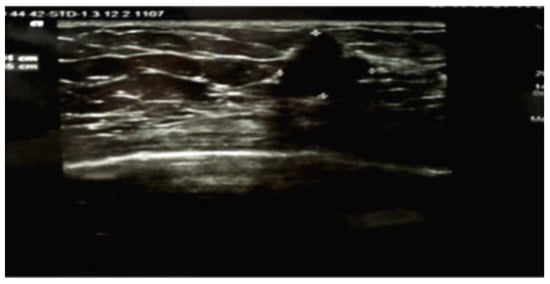

Bilateral mammography identified breasts with predominantly adipose tissue structure and symmetric appearance, without suspicious microcalcifications. In the right breast gland, a posterior nodular opacity with unclear contours was visualized (Figure 2).

Figure 2. Images obtained from the right breast. A mediolateral oblique mammogram shows benign vascular microcalcifications. Nodular opacity with blurred outline, spiculated at places, with a microcalcification inside it, the posterior outline is not visualized - BI-RADS 4C.

The imaging appearance of mucinous breast carcinoma can be confused with a benign lesion as it sometimes presents as a round-shaped mass with clear margins on mammography []. In some cases, mucinous breast carcinoma can be mammographically subtle or yield inconclusive mammographic results, such as calcifications, opacities, or focal asymmetries []. In most cases, mucinous breast carcinoma appears on mammography as a low-density mass, round or oval in shape, with tumor margins that can range from microlobulated (high mucin content) to irregular or spiculated (low mucin content). The mucin content is correlated with peripheral features.

Our patient presented with a mixed mucinous breast carcinoma without axillary lymph node invasion, with a spiculated appearance and a challenging mammographic interpretation. A definitive mammographic conclusion was only possible after repeating the computed tomography examination and performing serial mammograms with atypical features.